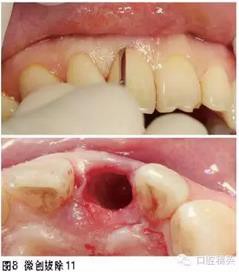

治療過程

2.使用不翻瓣技術(shù)在拔牙窩即刻植入種植體,不僅可使水平向和垂直向的骨吸收減少,而且有利于促進(jìn)相鄰位點(diǎn)鄰間骨高度的維持。